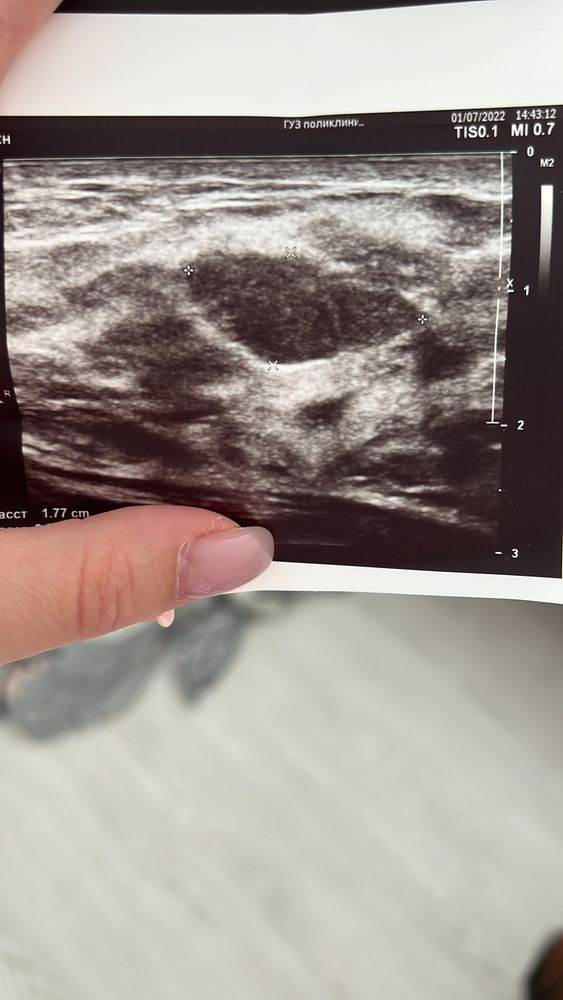

Евгения, вот что на узи обнаружили Изображение